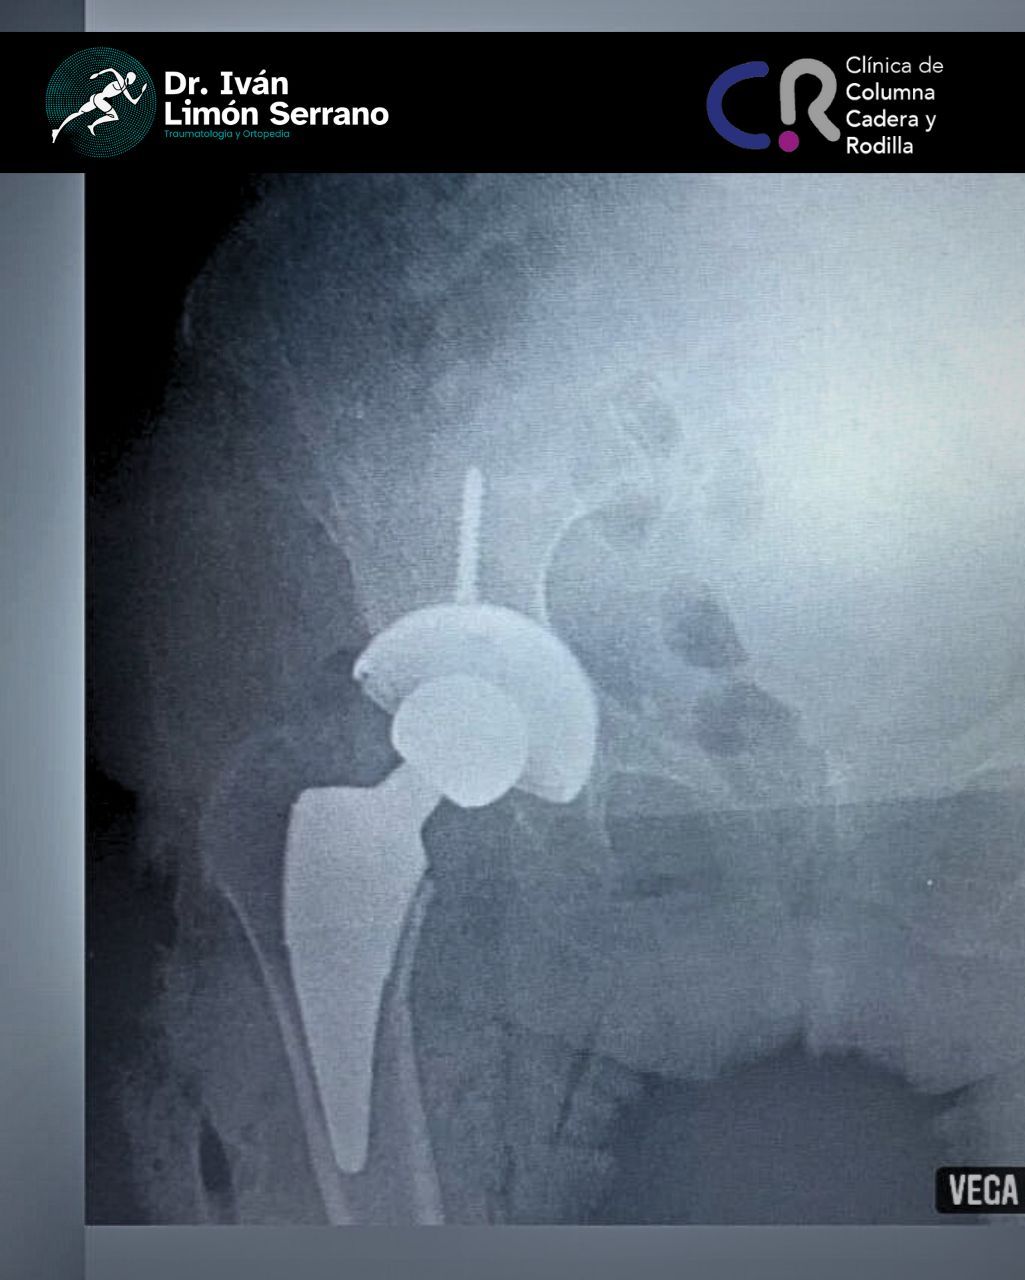

• Prótesis de cadera

• Cirugía cadera

Es una enfermedad articular caracterizada por la por degeneración, perdida del cartílago y alteración del hueso subcondral asociado a cambios en tejidos blandos. Se caracteriza por dolor articular, limitación funcional, crepitación y grados variables de inflamación. Factores de riego como sobrepeso, obesidad, debilidad muscular, actividad física pesada traumatismos, edad avanzada, sexo femenino, factores genéticos, trastornos metabólicos y congénito. Actualmente existen tratamientos desde lo no farmacológico control de peso hasta el tratamiento quirúrgico como lo es el reemplazo articular mediante la colocación de prótesis total.